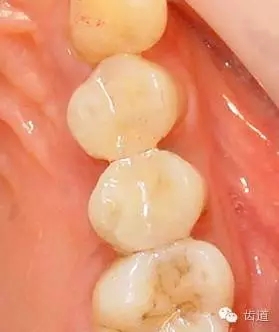

1、上頜前磨牙銀汞充填后食物嵌塞

2、去除銀汞充填物并作嵌體牙體預(yù)備

3、樹脂暫時(shí)嵌體覆蓋窩洞

4、瓷嵌體制作

5、瓷嵌體粘結(jié)